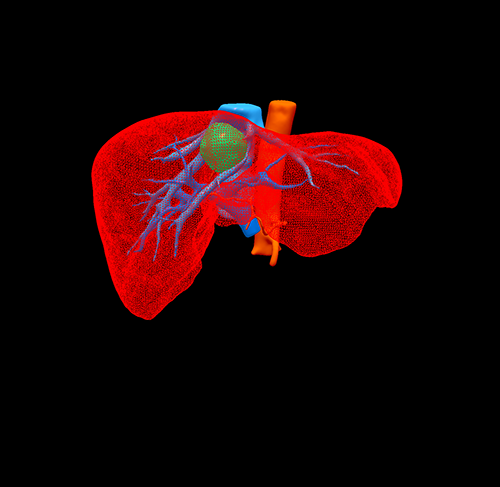

三维重建

S8肝癌---改良肝中叶切除(3D打印)